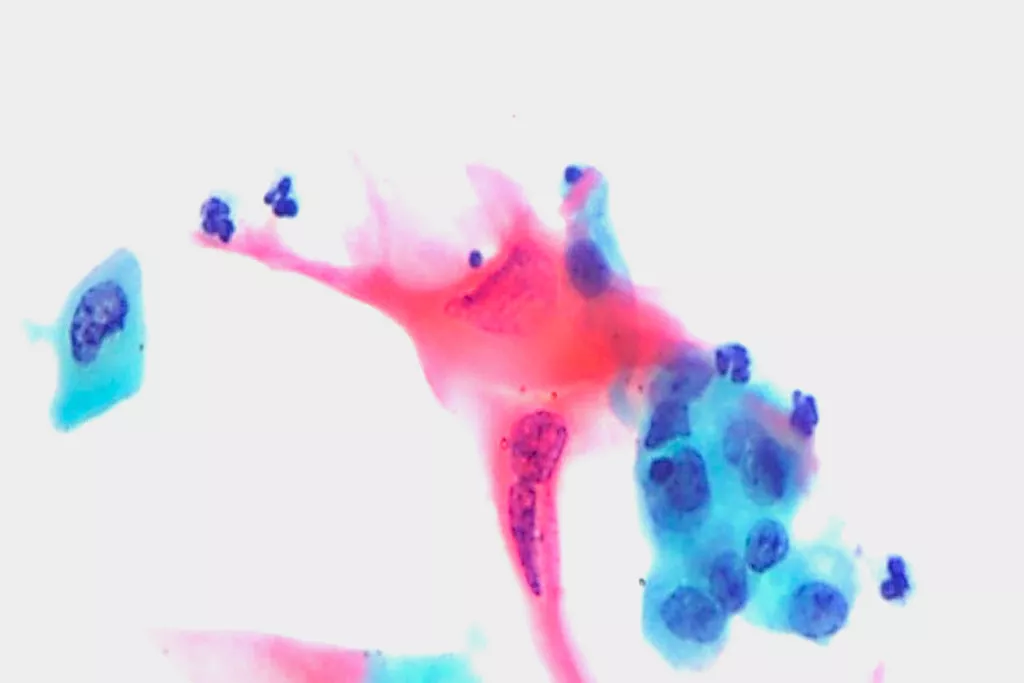

視覚化

軽度異型扁平上皮内病変 (LSIL) およびより重度の病変 (HSIL) の検出において、従来のパップスメアよりも向上しています2

従来のパップテストと比べて、腺疾患をの検出において向上しています2

画像ギャラリー9

9. ウェールズのランダウ病院細胞病理科から提供された画像